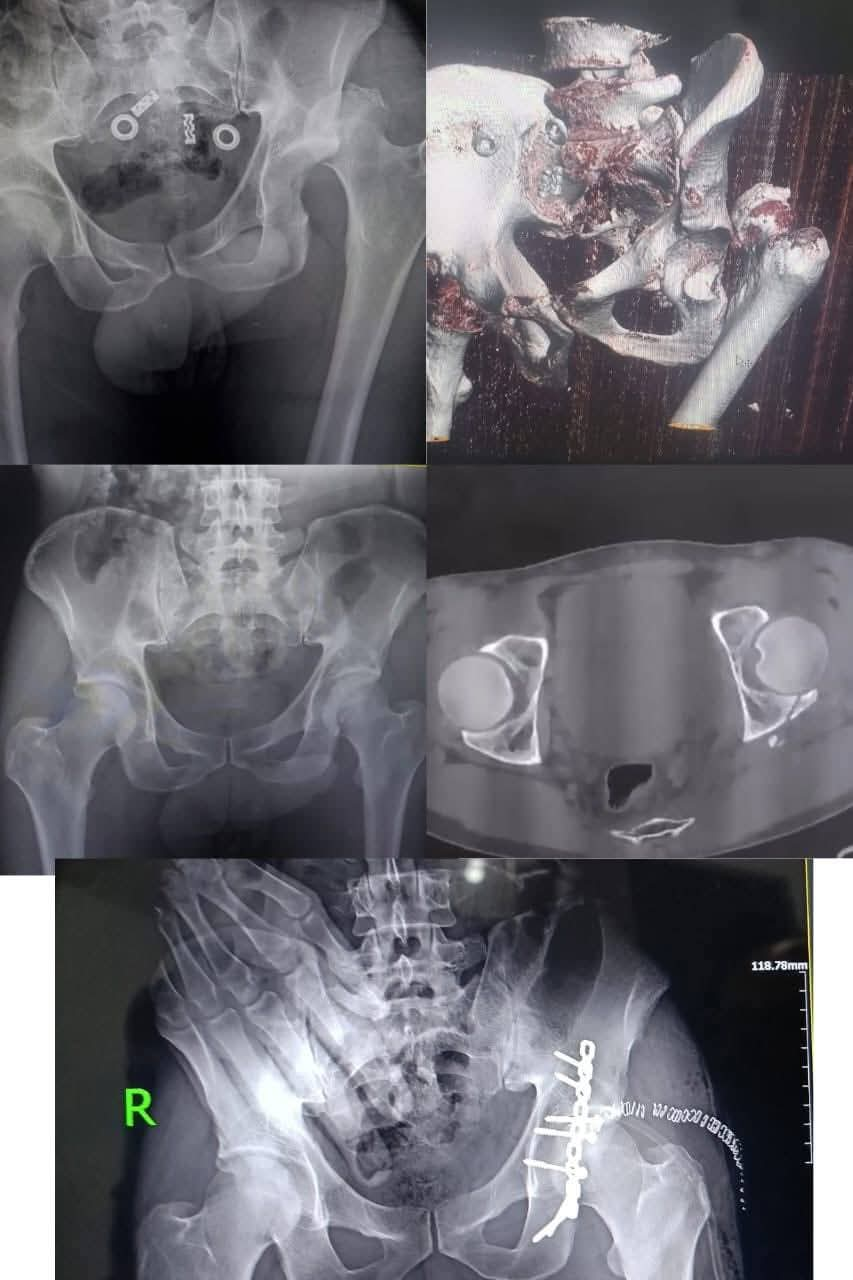

نجحت الفرق الطبية بمستشفى بركة السبع المركزي بمحافظة المنوفية، في إجراء جراحة طارئة ومعقدة بمفصل الحوض لأول مرة داخل المستشفى، وذلك لمصاب يبلغ من العمر 33 عامًا تعرض لحادث سير، وأسفرت العملية عن إنقاذ المريض واستعادة المفصل لوضعه الطبيعي.

كان قسم الطوارئ بالمستشفى قد استقبل المصاب وهو يعاني من كسر مضاعف وخلع بمفصل الحوض الأيسر، حيث جرى تقديم الإسعافات اللازمة، ورد الخلع داخل الطوارئ على يد الفريق الطبي بقيادة الدكتور أحمد النعماني، والدكتور خالد عمرو، وبمساعدة فني العظام محمود مجدي.

بعد استقرار الحالة، تم تجهيز المريض لإجراء الجراحة العاجلة التي استغرقت قرابة ساعتين ونصف، ونجح خلالها الفريق الطبي في تثبيت الكسور باستخدام شرائح ومسامير، والتأكد من عودة المفصل إلى وضعه الطبيعي.

أُجريت الجراحة تحت إشراف الأستاذ الدكتور الشربيني علي، استشاري ومدرس جراحة العظام، وبمشاركة الدكتور أحمد النعماني، والدكتور أحمد نصار، والدكتور أحمد جمال، وبمساندة فريق التخدير بقيادة الدكتور محمد جمال البلشي، والدكتورة ولاء محمد، إلى جانب أطقم التمريض والتخدير والأشعة والصيدلة.